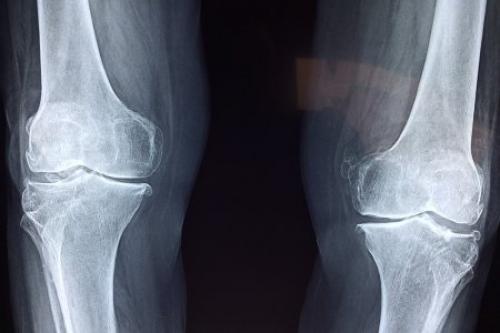

Несколько миллионов человек на Земле страдают остеопорозом. При этом недуге происходит ослабление костей, что они становятся чрезвычайно хрупкими. Именно мозг поможет предотвратить этот недуг, считают исследователи из университетов Лос-Анжелеса и Сан-Франциско.

Учёные поясняют, что у человека в норме происходит обновление кости за счёт появления новой ткани. У больных остеопорозом этого не происходит, сам цикл обновления ткани костей нарушен и восполняет костную ткань не в полном объёме.